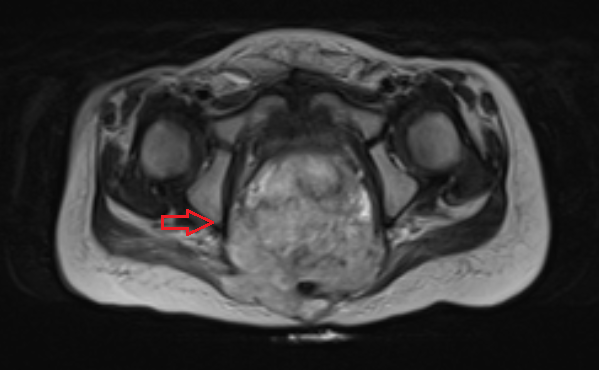

- КТ (расшифровка: компьютерная томография), МРТ (расшифровка: магнитно-резонансная томография), ПЭТ-КТ (расшифровка: позитронно-эмиссионная томография, совмещенная с КТ). Эти обследования необходимы, чтобы рассмотреть структуры организма послойно и визуализировать опухоль. Они показывают, как сильно распространен патологический опухолевый процесс на находящиеся рядом ткани и органы, есть ли поражение костей. КТ - это самый чувствительный метод для обнаружения метастазов в легких. Проведение МРТ и КТ головного мозга необходимо, чтобы обнаружить и визуализировать герминогенные новообразования эпифиза.

Диагноз устанавливается с учетом жалоб, анамнеза, результатов внешнего осмотра, лабораторных и инструментальных исследований. Пациентов с подозрением на семиному направляют на УЗИ органов мошонки. Для выявления метастазов назначают рентгенографию грудной клетки, КТ брюшной полости, МРТ печени, сцинтиграфию костей скелета и другие исследования. В процессе дифференциальной диагностики семином и других злокачественных новообразований яичка используют анализы крови на онкомаркеры.

Компьютерная томография органов грудной клетки, брюшной полости, малого таза используются для оценки распространения опухолевого процесса (рис.5).